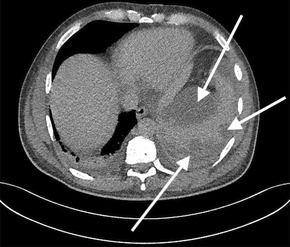

He completed seven days of broad‐spectrum antibiotics, and doxycycline was continued pending serology. A serial CT scan of the chest, abdomen and pelvis was performed to further investigate the cause of sepsis and demonstrated an incidental grade four splenic injury with peri‐splenic and subcapsular collections (Box 2). With a stable haemoglobin level, he was managed conservatively.

Box 2 – Grade four splenic injury with peri‐splenic and subcapsular collections

*The arrows indicate the splenic injury.